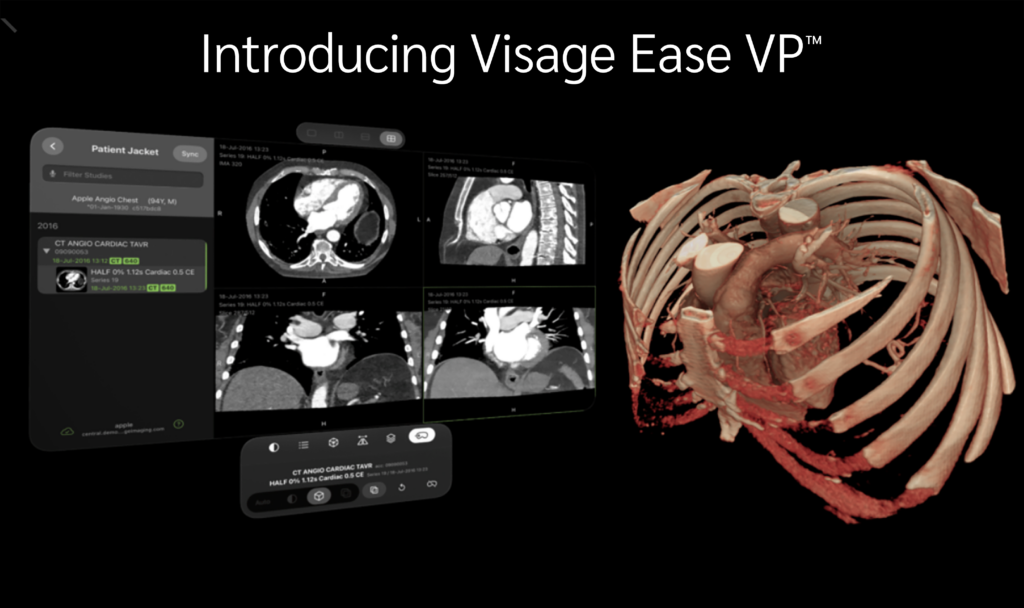

Visage Launches Visage Ease VP™ for Apple Vision Pro Visage Imaging

Visage Launches Visage Ease VP™ for Apple Vision Pro Visage Imaging Ihc Visage Radiology 52 the medical imaging community is embracing machine learning (ml) and artificial 53 intelligence (ai) to. visage 7 is a system for distributing, viewing, processing, and archiving medical images in healthcare environments. visage ease pro is a mobile client for diagnostic image viewing of radiological images from the following modalities: Viewing radiology images within the. access. Ihc Visage Radiology.